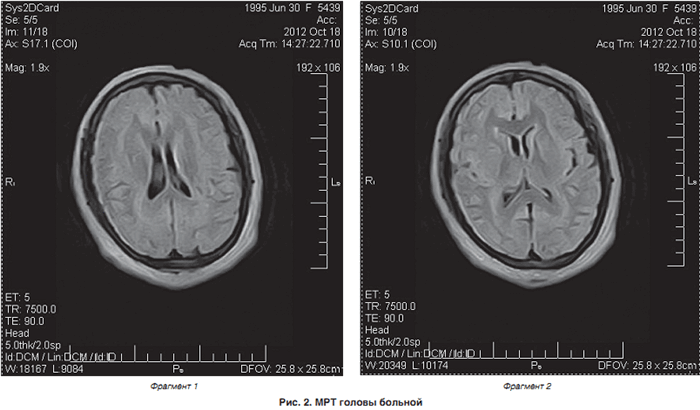

Кроме того, была проведена магнитно-резонансная томография головного мозга (аппарат Hitachi Airis Mate 0,2 Тесла), согласно которой на аксиальных срезах определялись билатеральные лентовидные зоны, соответствующие серому веществу головного мозга, расположенные преимущественно субкортикально. Изгибы гетеротопированных слоев повторяли основную складчатость кортикальной поверхности. На коронарных срезах подтверждалось субкортикальное расположение гетеротопированных зон. В коре видимых диспластических изменений не отмечено. Таким образом, можно утверждать о наличии у пациентки МР-признаков билатеральной ламинарной гетеротопии серого вещества, что характерно для синдрома «двойной коры» (рис. 2).

![]() |

Таким образом, у больной отмечался ранний дебют эпипароксизмов со специфической динамикой и наслоением пароксизмов: фокальные – вторичная генерализация – астатические – аутомоторные пароксизмы, нарастающий когнитивный и неврологический дефицит, преобладание фокальной эпилептической активности на ЭЭГ и, наконец, наиболее значимый диагностический критерий – МР-признаки ламинарной гетеротопии серого вещества. В ходе обследования был выставлен диагноз: «аномалия развития центральной нервной системы: билатеральная ламинарная гетеротопия серого вещества головного мозга – синдром «двойной коры», эпилептическая энцефалопатия Леннокса – Гасто».